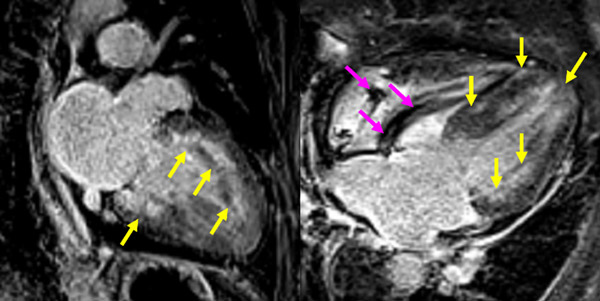

Figure 4A : Séquence de rehaussement tardif - Coupes petit-axe

Figure 4B : Séquence de rehaussement tardif - Coupes long-axe 4 cavités et 2 cavités

Figure 8A : Séquence de rehaussement tardif - Coupes petit-axe

Figure 8B : Sequence de rehaussement tardif - Coupes long-axe 4 cavités et 2 cavités

Point technique

Les séquences de rehaussement tardif visualisées ici sont des séquences PSIR et non des séquences de rehaussement tardif en magnitude du fait d’une difficulté fréquente à la détermination du temps d’inversion (Ti) en cas d’amylose cardiaque.

- Présence d’un rehaussement tardif diffus sous-endocardique circonférentiel à l’ensemble du VG (flèches jaunes). Notez également le rehaussement tardif marqué de la paroi de l’oreillette gauche (OG) visible en 2 et 4 cavités.

- De plus, on visualise la présence d’un épanchement péricardique de moyenne abondance qui apparait toujours en noir sur des séquences PSIR (flèches rouges).

- À noter, la visualisation de la sonde de PM avec artéfacts métalliques modérés au niveau du ventricule droit (flèches roses).